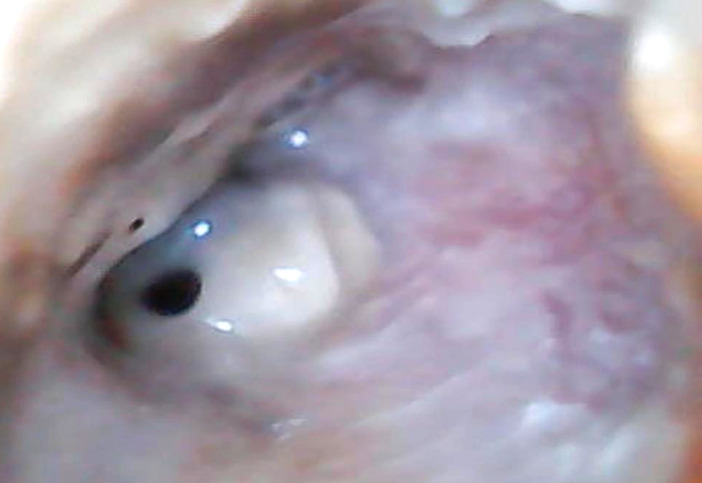

Introduction/rationale: Tuberculosis remains a major public health issue. It is an opportunistic pathology, very common in HIV-immunocompromised persons, classifying it at the WHO stage 4. Ear tuberculosis remains a rare and under-diagnosed clinical form. We report here a case of ear tuberculosis concomitant with pulmonary localization in an HIV-immunosuppressed person on triple antiretroviral therapy aged 32 years hospitalized in Bamako (Mali) to discuss the diagnostic and therapeutic difficulties posed by this rare localization.

Description of the case: The patient had a chronic productive cough, otalgia and right chronic purulent otorrhea. The search for acid-resistant bacilli was positive for direct examination in gastric casing fluid and swabbing of the ear pus, confirming the diagnosis of tuberculosis. Anti-tuberculosis treatment instituted for 6 months associated with adjuvants resulted in complete healing of the patient.